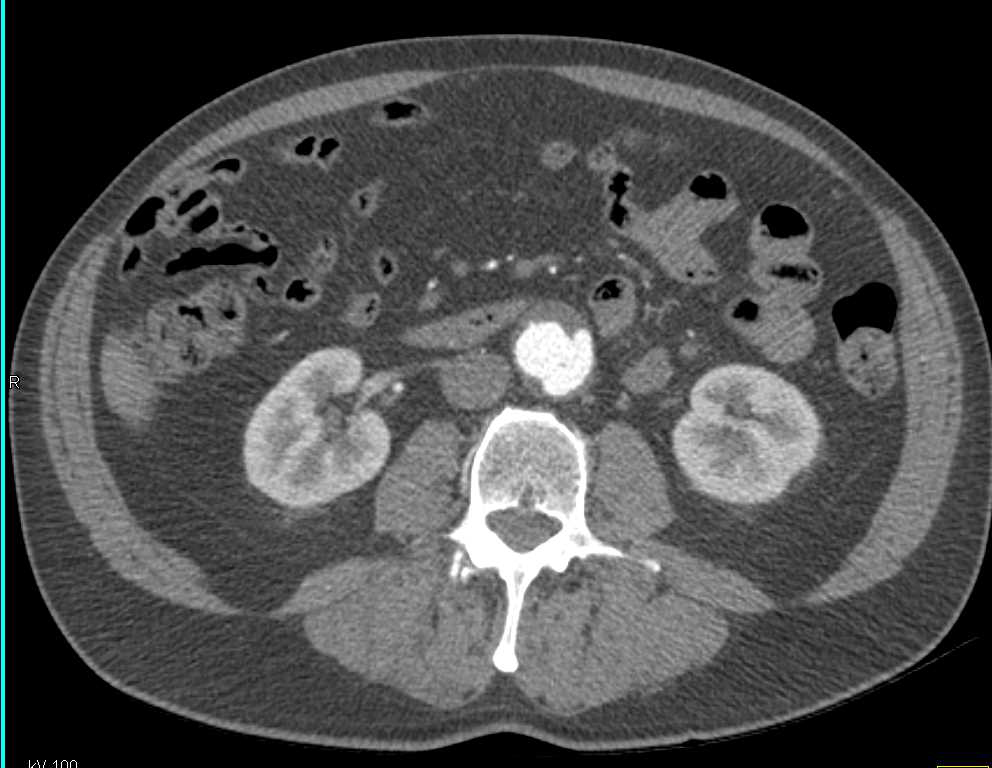

Non-opaque Stone in the Distal Common Bile Duct